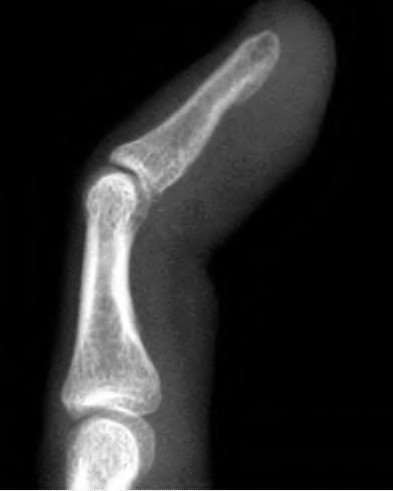

volar tenderness along the flexor sheath

Patients commonly present 24 to 48 hours after onset of symptoms. The standard of care is “urgent surgical drainage” to avoid tendon scarring or necrosis with subsequent impairment of finger function followed by intravenous antibiotic administration.

According to Hand Surgery Update 3, open sheath irrigation has been replaced

largely by closed sheath irrigation. These authors cite a retrospective study that showed no statistical difference in resolution of infection using open sheath irrigation or closed sheath irrigation, however, there was a trend towards more frequent complications and reoperations in the open drainage group.

Lille et al reviewed the records of 75 patients with pyogenic flexor tenosynovitis and found that there was no difference in outcomes between those who received intraoperative irrigation only versus those receiving intraoperative irrigation and continuous postoperative irrigation.